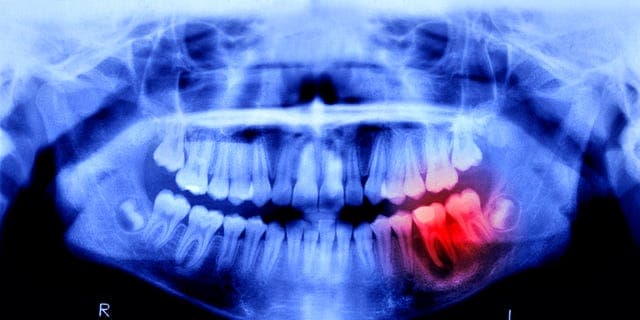

Humans May Be Able to Grow New Teeth Within Just 4 YearsTLDRJapanese researchers have begun human trials for a drug that could enable tooth regrowth, with hopes of making it available for all forms of toothlessness by 2030.